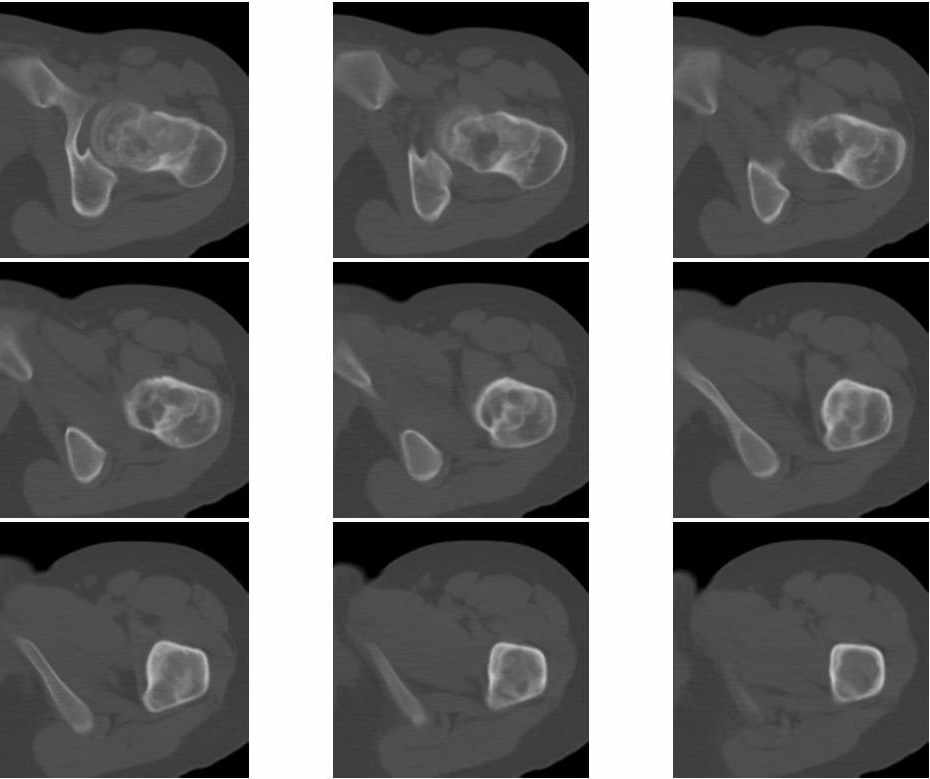

Молодая женщина 18 лет, последние 3 года стали беспокоить боли в левом тазобедренном суставе.

На рентгенограмме, утолщена шейка бедра и в шейке участок просветления. При КТ шейка утолщена на 9мм, в шейке полость24х21мм, стенки полости неровные и нечеткие, за пределы коркового слоя полость не выходит. Плотность содержимого полости 43 ед.Н. Предположительно должна быть солитарная киста шейки бедра, но смущает неровность и нечеткость контуров стенок. Ваше мнение господа? Какой предложите доступ для биопсии.Приложена первая серия снимков.